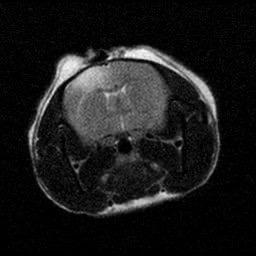

Figure 2. (A-B) Representative MRI images showcasing the lesioned brain area ofChrdl1 Ckoand Cre(-)mice at1daypost-stroke and 7days post-stroke. (C) Bar graph comparison of stroke volume between Cre (-) andCkomice,1dayand7dayspoststroke.Statisticaldifferencesbetween groups or time points, where applicable, are indicated by asterisks (*p< 0.05, **p<0.01). (D) Line graph comparison of stroke area percentage betweenCre(-)andCkomice,1dayand7dayspoststroke.